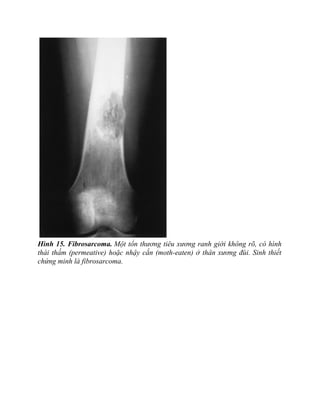

Fibrosarcoma

Fibrosarcoma là khối u tiêu xương ác tính không sinh xương hay chất cơ bản

sụn. Chúng thường không gây ra phản ứng tạo xương và do đó hầu như luôn có

hình tiêu xương. Hình thái tiêu xương này có bất cứ dạng nào, từ dạng thấm

(permeative), tới dạng “nhậy cắn”- “ moth eaten” (hình 15) tới một mảng tiêu

xương rõ (hình 16). Nó có thể khiến chẩn đoán X quang rất khó khăn.

Hình 15. Fibrosarcoma. Một tổn thương tiêu xương ranh giới không rõ, có hình

thái thấm (permeative) hoặc nhậy cắn (moth-eaten) ở thân xương đùi. Sinh thiết

chứng minh là fibrosarcoma.